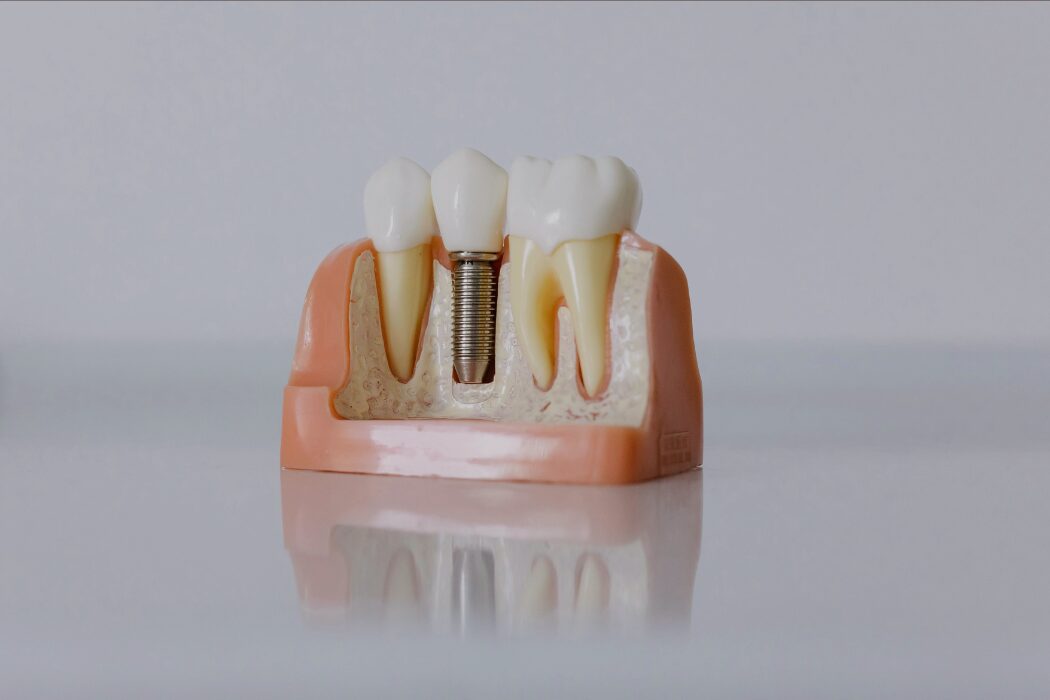

Un implante dental no es solo colocar un tornillo. Detrás hay diagnóstico, planificación y un proceso preciso para recuperar función y estética de forma estable.